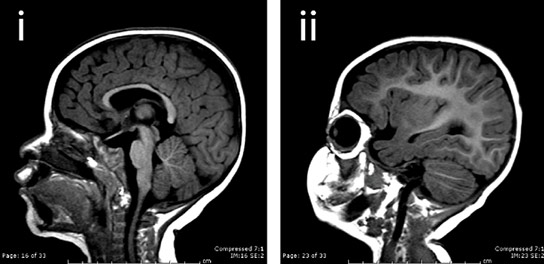

一个普通的大脑和一个有微微畸形的人。

甘尔集团表明,在佩戴生物中,从斑马鱼到果蝇,沉默的KatnB1导致大脑大小降低。突变严重影响不对称,而不是对称的细胞键。不对称细胞键可通过在每种术中产生“祖母”和“女儿”电池来补充神经干细胞群。这允许在早期脑发育期间对细胞数量的指数增加,这在突变KatnB1中丢失了脑中。

“人们普遍理解,不对称细胞间术语在脑皮质发展中起着至关重要的作用,”Gunel说。“Katnb1突变的发现现在揭示了这种机制的基本重要性的一个美观例子以及如何丧失非对称细胞锁定导致小脑尺寸的损失。”